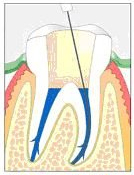

Im Röntgenbild von Abb. 3 ist ein gut erbsengrosses Granulom (Pfeil) an der Wurzelspitze eines toten, devitalen Zahnes feststellbar. Die Patientin wünschte die Erhaltung des Zahnes, zumal auch der vordere Nachbarzahn marktot und beherdet war. Abb. 4 zeigt das Röntgenbild nach der Wurzelfüllung.

Ein halbes Jahr später hat die Patientin sich dazu entschlossen, den vorderen beherdeten Zahn auch endodontisch behandeln zu lassen. An Abb. 5 wird im Röntgenbild die Wurzellänge mit Instrumenten bestimmt. Man gewinnt auch den Eindruck, dass der bereits vor einem halben Jahr wurzelbehandelte Zahn in Abheilung sei.